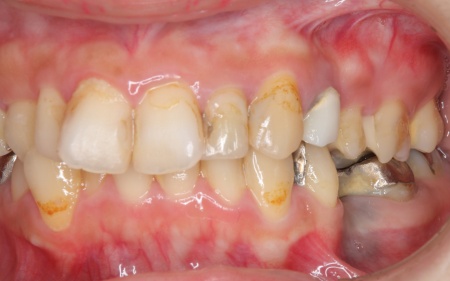

20代女性 ワイヤー矯正で歯並びを整えて虫歯治療やインプラント治療で口腔内全体を改善した症例

詳しく拝見したところ、下の前歯4本を除くほぼすべての歯に虫歯が認められました。 また、左上奥歯1本と左下奥歯1本が欠損しており、その影響で噛み合わせのバランスが崩れているため、噛んだときの痛みにつながっていると考えられます。 このまま放置すると、虫歯が進行したり、欠損部周囲の歯が動いて噛み合わせがさらに不安定になったりするリスクがあるため、虫歯を含めた口腔内全体の治療が必要だと診断しました。 |

治療前